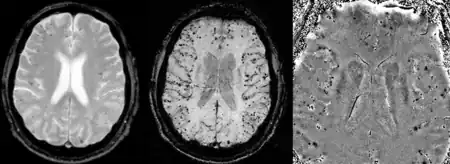

CAA can only be definitively diagnosed by a post-mortem autopsy.[27] Biopsies can play a role in diagnosing probable cases.[28] When no tissue is available for biopsy, the Boston Criteria are used to determine probable CAA cases from MRI or CT scan data. The Boston Criteria require evidence of multiple lobar or cortical hemorrhages to label a patient as probably having CAA.[27] Susceptibility weighted imaging has been proposed as a tool for identifying CAA-related microhemorrhages.[29]

Cerebral amyloid angiopathy can be presented with lobar intracerebral hemorrhage or microbleeds in the brain. The bleeding usually occurs on the surfaces of the brain in contrast with intracranial haemorrhage due to high blood pressure which occurs in deep locations of the brain such as basal ganglia and pons. In lobar intracerebral bleed, computed tomography (CT) scan would show hyperdense haemorrhage area and hypodense odema around the haemorrhagic site.[19]

MRI sequence of gradient echo and susceptibility weighted imaging (SWI) are useful in detecting microbleeds and deposition of iron on the brain cortex (cortical superficial siderosis).[19] Other MRI indicators of CAA include white matter hyperintensities and cortical thinning.[30]